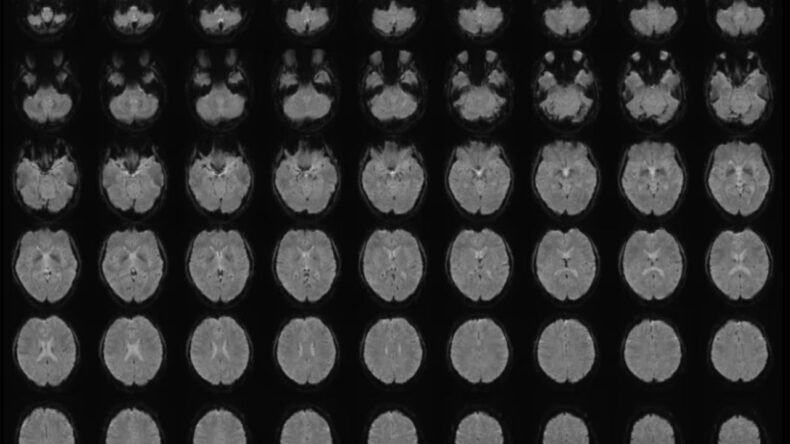

Katılımcılar, içinde nesneler, sahneler ve eylemler bulunan 2180 kısa ve sessiz video izlerken beyinleri fMRI ile tarandı. Videoların altyazıları, büyük dil modelleri aracılığıyla sayısal dizilere dönüştürüldü.

Horikawa, taranan beyin aktiviteleri ile bu sayısal verileri eşleştirecek “çözümleyici” modeller geliştirdi. Bu modeller, daha önce hiç görmediği videoları izleyen katılımcıların beyin aktivitelerini çözümleyerek bu aktivitelere en uygun cümleleri oluşturdu.